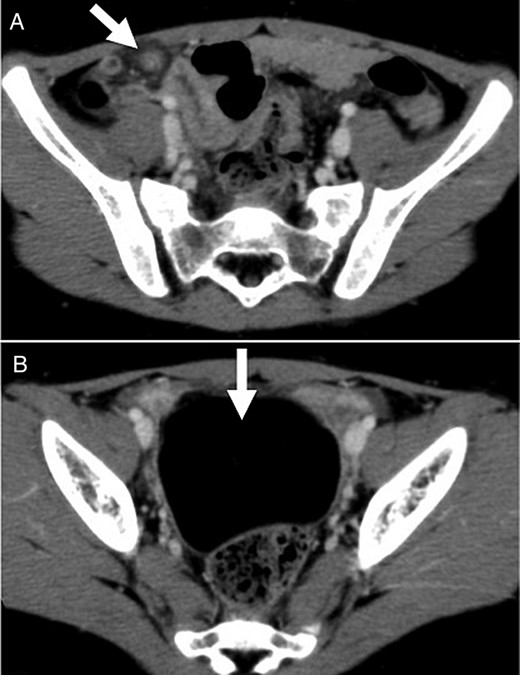

A 5-year-old Japanese preschool girl presented with a 1-week history of right lower abdominal pain of increasing severity that was associated with nausea and anorexia. She had no history of similar episodes of abdominal pain. On physical examination, her temperature was 38.1°C and her abdomen was tender in the right lower quadrant with signs of peritoneal irritation. No masses were palpable. Laboratory investigation revealed a white blood cell count of 10 000/mm3 with 77% segmented neutrophils. No abnormalities were noted in the plain abdominal radiograph. A contrast-enhanced computed tomography (CT) scan of the abdomen revealed linear folds of omental tissue in a concentric pattern that extended from the level of the transverse colon to the right lower abdomen (Fig. 1A). A pelvic mass of 6 cm in diameter with the same uniform radiodensity as that of fatty tissue was also observed (Fig. 1B).

Contrast-enhanced CT scan showed (A) torsion of the omentum, which was seen as linear folds of omental tissue in a concentric pattern that extended from the level of the transverse colon to the right lower abdomen; and (B) a pelvic mass of 6 cm in diameter with the same uniform radiodensity as fatty tissue.